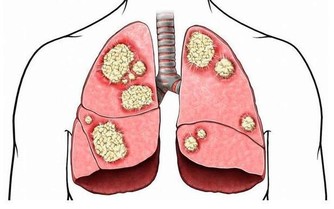

正常健康腳掌顏色應是白裡透紅,如果腳掌發白,無血色,可能是血液垃圾過多,致使血管淤堵,供給腳掌的血液不夠,腳掌自然呈現出發白的症狀,出現這種情況且伴有頭暈、眼花、無力等症狀時,應留意肝臟健康。

中醫學認為,正常腳底顏色略紅。排除一些角質層較厚的人會出現腳底發黃之外,還可能與肝臟有關係,當肝細胞破壞,使得血中的膽紅素不能正常的排除,逆流至血液中,呈現出腳底發黃。